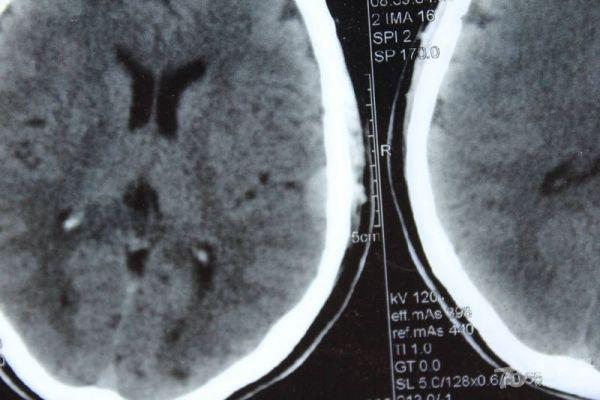

脑部占位病变CT,MRI图片,请帮忙诊断

最近感图样,无其它脑病病史

考虑脑膜瘤!!

磁共振没有平扫,增强矢状位没找到病灶。像脑膜瘤。

图片不是很清楚,应该是脑膜瘤!